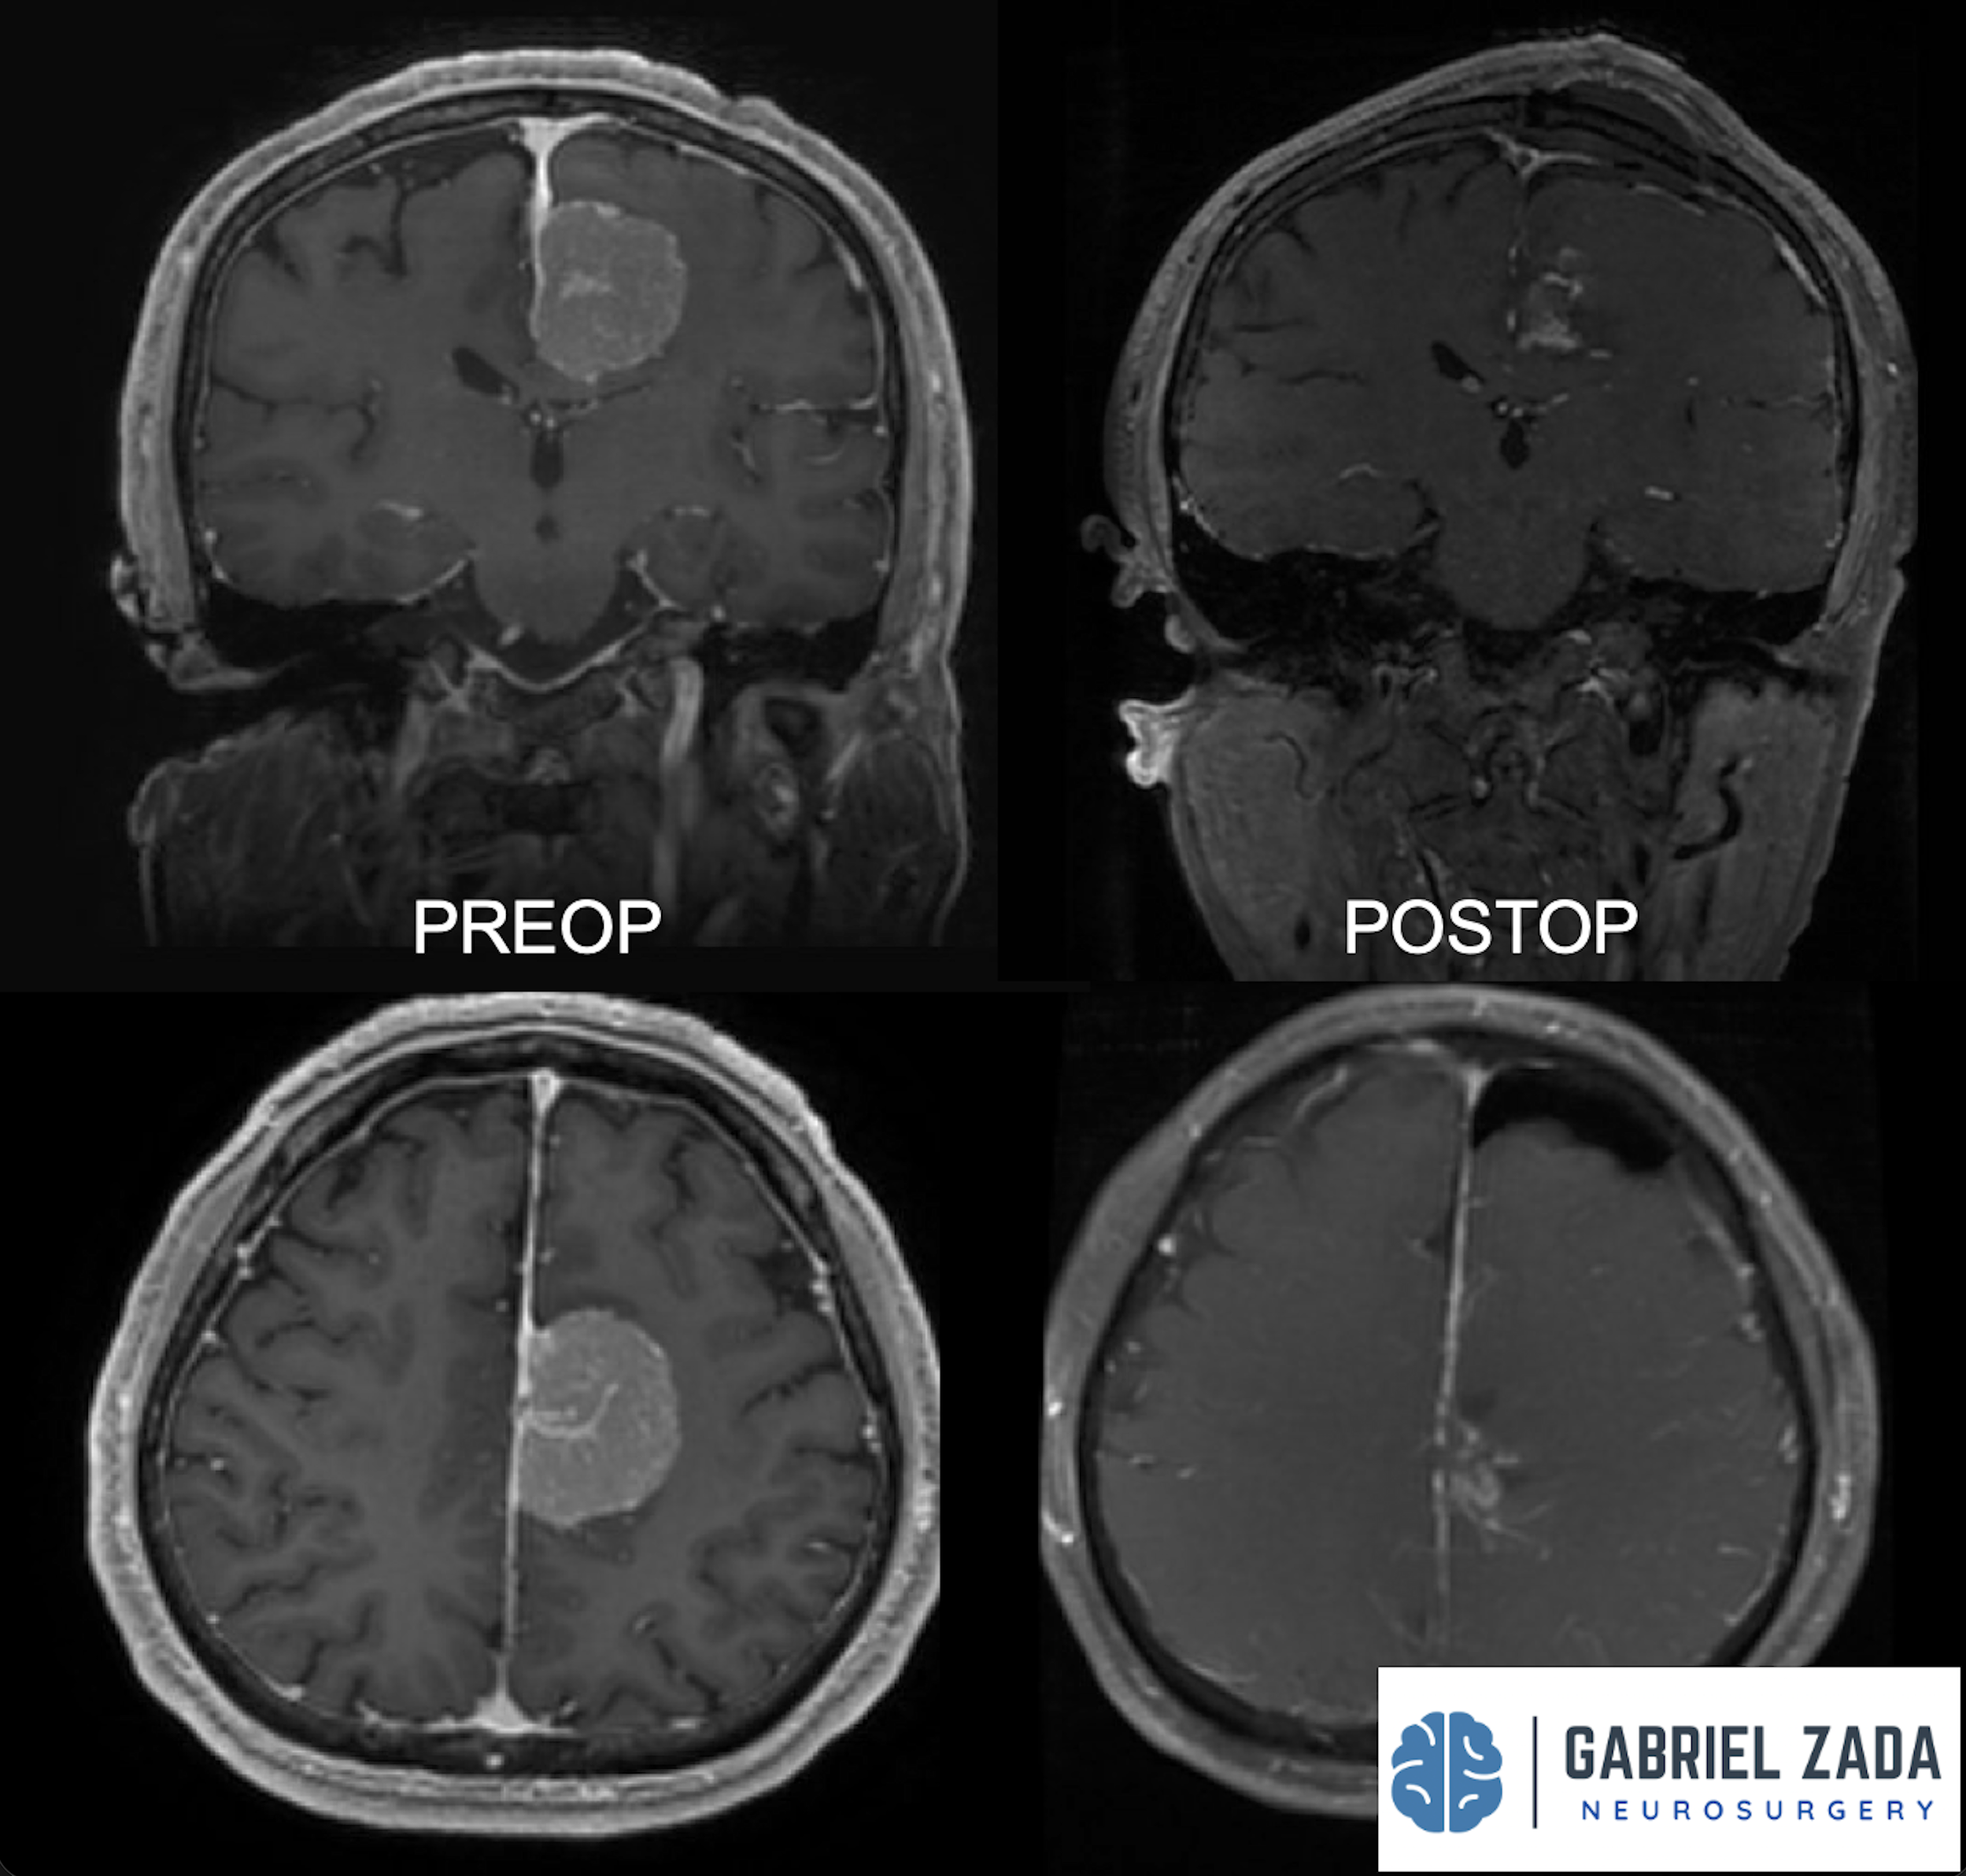

Explore this comprehensive gallery featuring pre‑ and post‑operative imaging of patients with skull‑base tumors treated by Gabriel Zada, MD, MS, FAANS, FACS. These cases highlight Dr. Zada’s expertise in advanced neurosurgical techniques and outcomes.

*Representative cases shown for educational purposes. All images de-identified. Individual results vary.